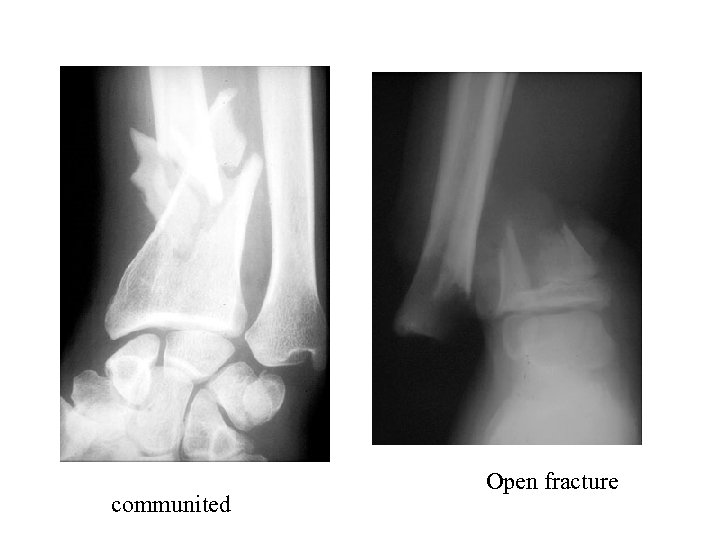

X-rays can provide information about: • Obstructions (blockage) • Tumors • Fractures • Other diseases & illnesses

X-rays can provide information about: • Obstructions (blockage) • Tumors • Fractures • Other diseases & illnesses

communited Open fracture

communited Open fracture